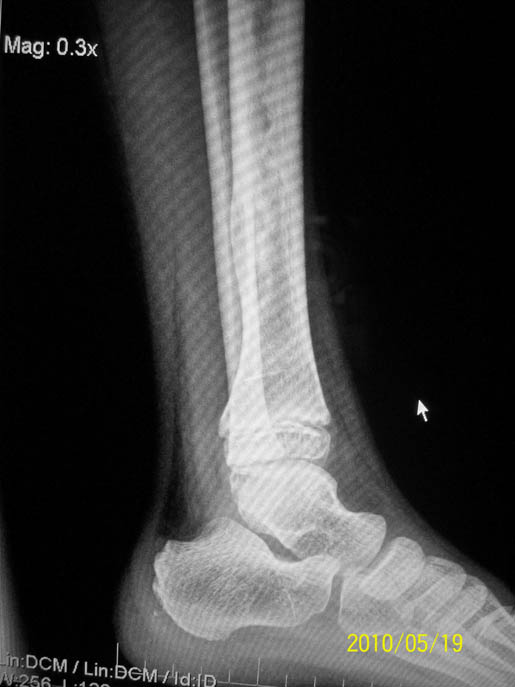

以下是引用随光逐影在2010-5-21 17:25:00的发言:[br]病例1:右胫骨下段非骨化性纤维瘤。[br]病例2:右股骨下段软骨黏液样纤维瘤?非骨化性纤维瘤?

以下是引用流星1234在2010-5-21 14:17:00的发言:[br]1.胫骨非骨化性纤维瘤。2.骨软骨瘤。